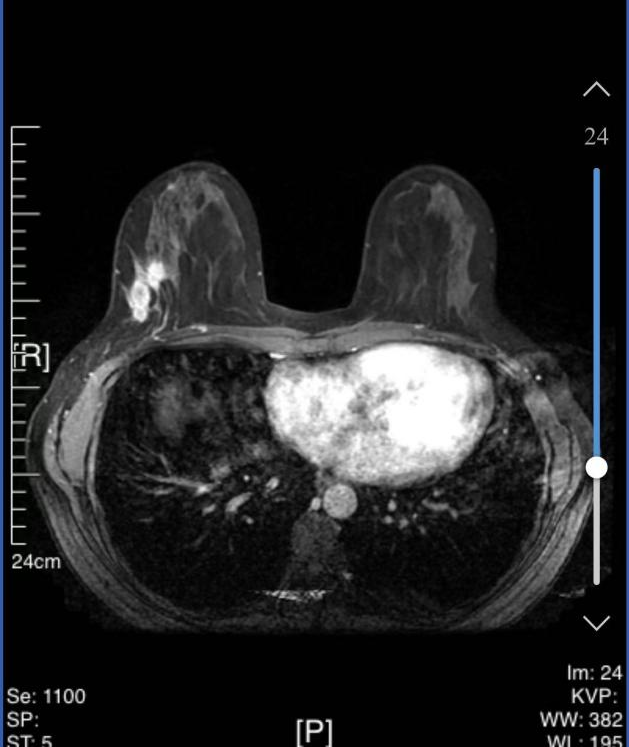

• 乳腺核磁共振(MRI):

1、右乳外侧象限见T2WI稍高信号肿物,大小约31mm*25mm*33mm,形态不规则,边缘分叶;内部强不均匀,TIC曲线初始呈快速强化,延迟期呈平台型;DWI呈高信号,ADC值为0.000811mm2/s。右腋窝见肿大淋巴结。

MRI提示:右乳外侧象限肿块及多处非肿块样强化,BI-RADS 5类;右腋窝淋巴结肿大。

图3 乳腺MRI结果(2024-03-04)